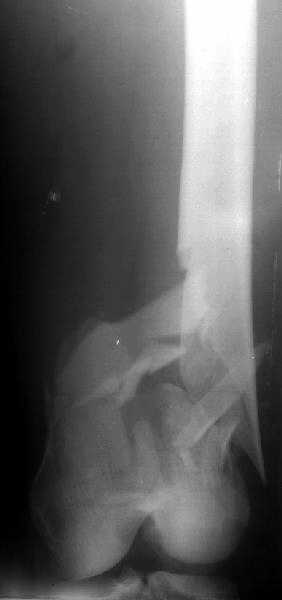

de> you think you are using antigrade nails for some very low

de> fractures including some intercondylar fractures.

Exactly. It seems the option looks underestimated.

de> And perhaps you could show us also some of your results ,

de> that is (follow up) not immediate postop x rays.

I attached an example of C2 fracture with result of the same technique in 5 months.